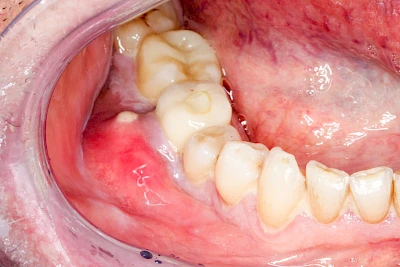

Sonderform: Abszess / Schwellung

Bei einem Abszess breiten sich Bakterien oder andere Erreger im Bereich der Kiefer und aufliegenden Weichteile aus, ohne gleich in die Mundhöhle durchzubrechen (siehe Fistel). Die schnelle starke Vermehrung und Einschmelzung von Bakerien und anderen Erregern führt zu einer meist sehr schmerzhaften und häufig sichtbaren Schwellung. Im weiteren Verlauf können Abszesse auch durch die Weichteile durchbrechen und Fisteln bilden. Zudem können im Kopf-Halsbereich Schwellungen (Ödeme) als sichtbares Zeichen der Körperabwehr auftreten.

Abszesse können, vor allem, wenn die Ausbreitung der Erreger im Körper über die Faszien und Logen voranschreitet, schnell zu einer Verschlechterung des Allgemeinzustands führen (z. B. Fieber) und sogar lebensbedrohlich werden. Deshalb ist sofort der Zahnarzt zu verständigen. Ist dieser nicht erreichbar, sollte der Notarzt gerufen werden.